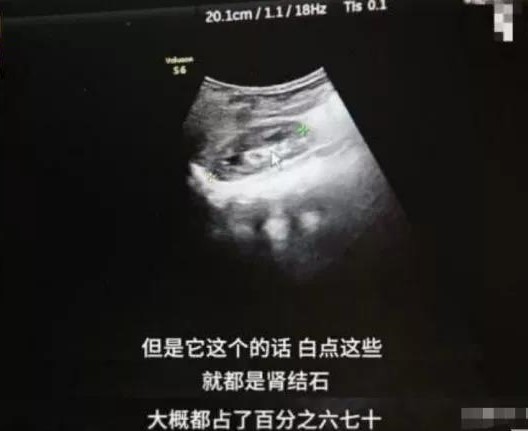

肾结石:

像文章开头提到的宝宝,长期补钙过量,造成了高钙尿症,尿液每次经过肾脏的时候,就会和草酸盐结合形成草酸钙,进而造成结石。这个宝宝只有9个月,无法手术,只能多喝水,自己排出结石。

患有肾结石是很痛苦的,发病的时候,疼痛难忍,相信每一个妈妈都不会希望小小的孩子遭受这样的痛苦,所以,千万不要给宝宝盲目补钙。